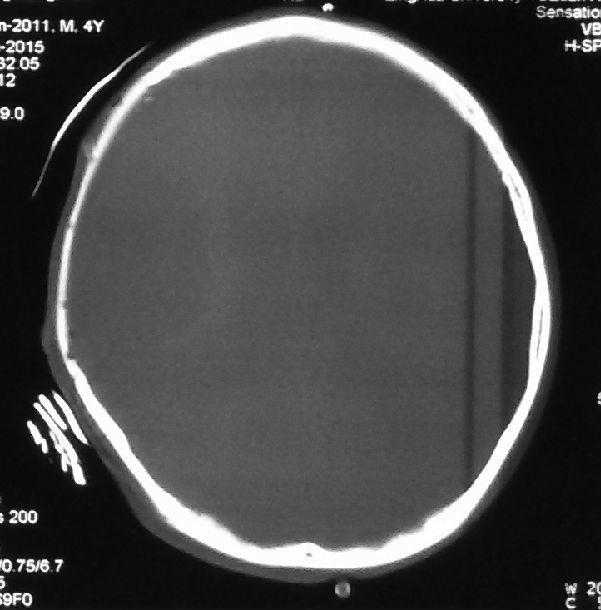

病例一:刘某某,男,4岁。额顶颅骨缺损,修补材料:清华仿生骨。